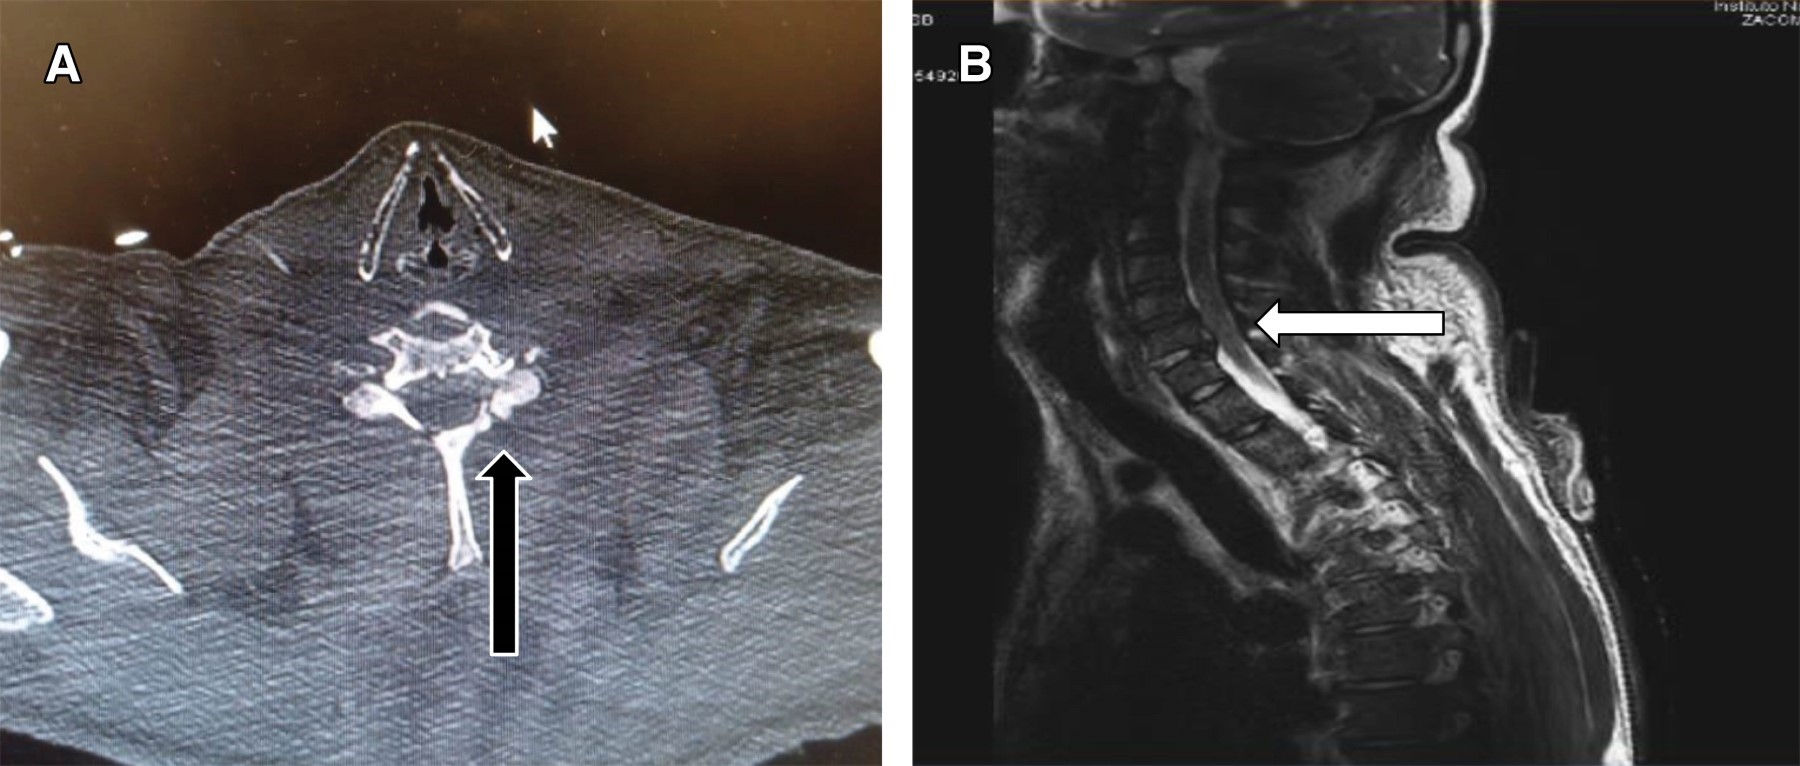

Hombre de 37 años con diagnóstico de quemadura eléctrica + fulguración de 17.7% superficie corporal quemada (SCQ) (Figura 1). Presentó politraumatismo secundario a caída de cinco metros de altura con pérdida del estado de alerta y amnesia postraumática al ser proyectado por arco voltaico. Al ingreso con evaluación neurológica, Glasgow de 15 puntos, con disminución de fuerza en ambos miembros superiores 3/5 escala de Daniels bilateral, sensibilidad superficial y profunda conservada; como protocolo de estudio de paciente politraumatizado se solicitaron estudio se imagen: tomografía simple columna y resonancia magnética (Figura 2) con evidencia de fractura en C6 tipo A0, T5, T9, T11 tipo A1, fractura A4 de L5, herniación discal C6 y C7. Como complicaciones asociadas, cursó con lesión renal aguda por rabdomiólisis sin requerir tratamiento sustitutivo de la función renal.

Tomografía axial computarizada: estudio de imagen útil para descartar atrofia cerebral, contusiones, hematomas, hemorragias y fracturas secundarios a lesión directa por corriente eléctrica, así como asociados o no a caída como causa secundaria de la descarga.1,10,11

Resonancia magnética: puede mostrar el nivel exacto de la lesión debido a cambios en la señal de difusión. La médula espinal puede mostrar desmielinización local o extensa de la materia blanca, edema o infarto. Una lesión localizada a nivel de las astas anteriores puede afectar la motoneurona superior (lo que causa hiperreflexia) o la motoneurona inferior (lo cual ocasiona parálisis flácida).1,4,5,11